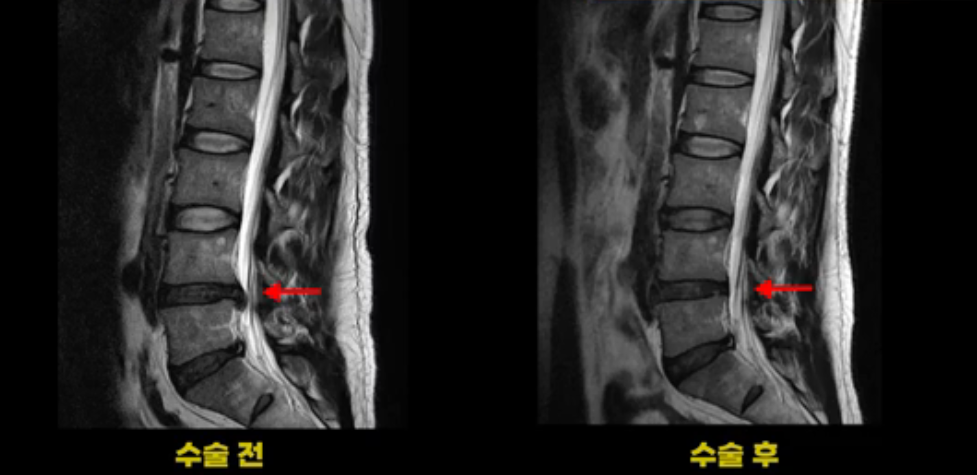

이 환자분은 디스크 파열 수술 후 3개월 정도 괜찮았다가 그 이후 점점 다리 저림과 통증이 다시 시작되어 수술 후 1년 정도부터는 거의 수술 전에 아팠던 정도까지 증상이 악화됩니다. 그런데 이분 수술 후 MRI를 보면 수술이 잘 돼서 깨끗합니다.

보시다시피 수술 전의 MRI와 비교해 보면 밀려 나온 디스크 수핵이 거의 대부분 깨끗이 제거되었습니다.